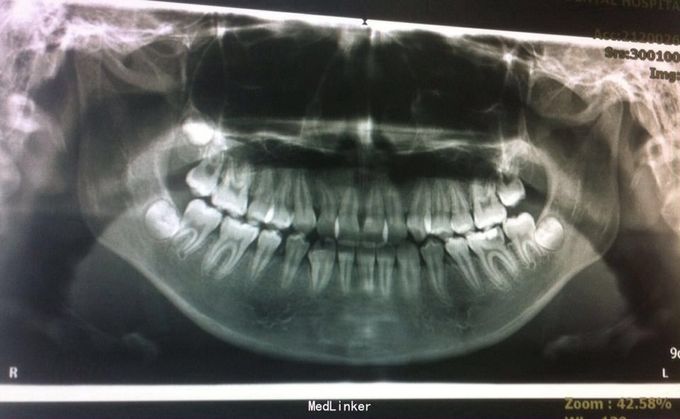

恒牙期 左右磨牙近中关系 12,22舌侧错位 32、33融合牙 右侧磨牙反合 上下牙列轻度拥挤 关节有弹响

安氏三类、后牙反合 不拔牙矫治,直丝弓矫治器,排齐整平上下牙列,解除后牙反合,矫治后覆合覆盖正常,磨牙中性关系,维持现有面型

治疗中可能需片磨上牙(下颌融合牙引起bolton指数不调)